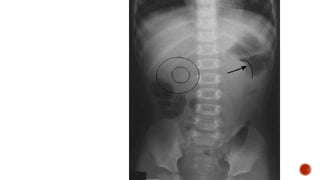

 Meniscus sign:

 Crescent of gas within colonic lumen that outlines the apex of intussusceptum.

 Little air in small intestine.

MENISCU

S

SIGN

 Convex intraluminal mass.

 May benormal.  Meniscus sign:  Crescent of gas within colonic lumen that outlines the apex of intussusceptum.  Little air in small intestine.